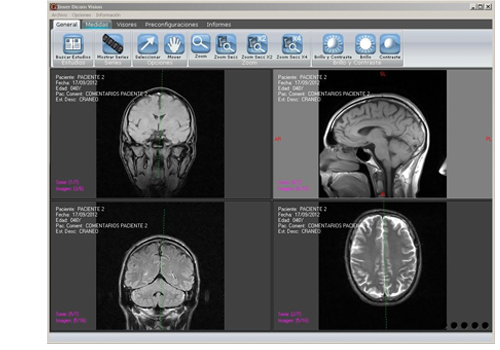

Las imágenes que obtenemos con la RM se entregan en formato digital DICOM vía online o bien en soporte CD. Desde la galería de imágenes os mostramos ejemplos de RM con patología e imágenes anatómicas normales..

Las imágenes que obtenemos con la RM se entregan en soporte CD/DVD junto al informe radiológico. Las imagenes obtenidas tienen un formato especial médico llamado DICOM, por lo que incluimos en el CD un software para poder visualizar las imagenes. Si Usted ya dispone de un visualizador DICOM, podrá importar las imágenes a su visualizador seleccionando la carpeta "DicomFiles" del CD

Las imágenes que obtenemos con la RM se entregan en soporte CD/DVD junto al informe radiológico. Las imagenes obtenidas tienen un formato especial médico llamado DICOM, por lo que incluimos en el CD un software para poder visualizar las imagenes. Si Usted ya dispone de un visualizador DICOM, podrá importar las imágenes a su visualizador seleccionando la carpeta "DicomFiles" del CDPóngase en contacto con nosotros por teléfono o por medio de nuestro formulario de contacto, estaremos encantado de atenderle.